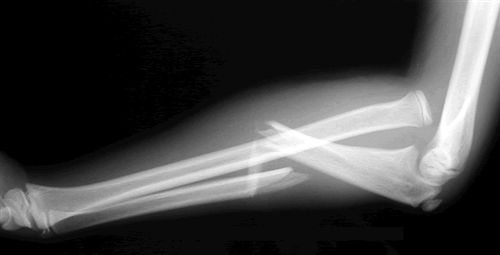

Monteggia injury

(fracture of the ulnar shaft and dislocation of the radial head at the elbow)

A _________ fracture involves fracture of the ulnar shaft and dislocation of the proximal radial head at the elbow, whilst a __________ fracture involves a fracture of the radial shaft alongside dislocation of the ulna at the distal radio-ulnar joint

A Monteggia fracture involves fracture of the ulnar shaft and dislocation of the proximal radial head at the elbow, whilst a Galeazzi fracture involves a fracture of the radial shaft alongside dislocation of the ulna at the distal radio-ulnar join